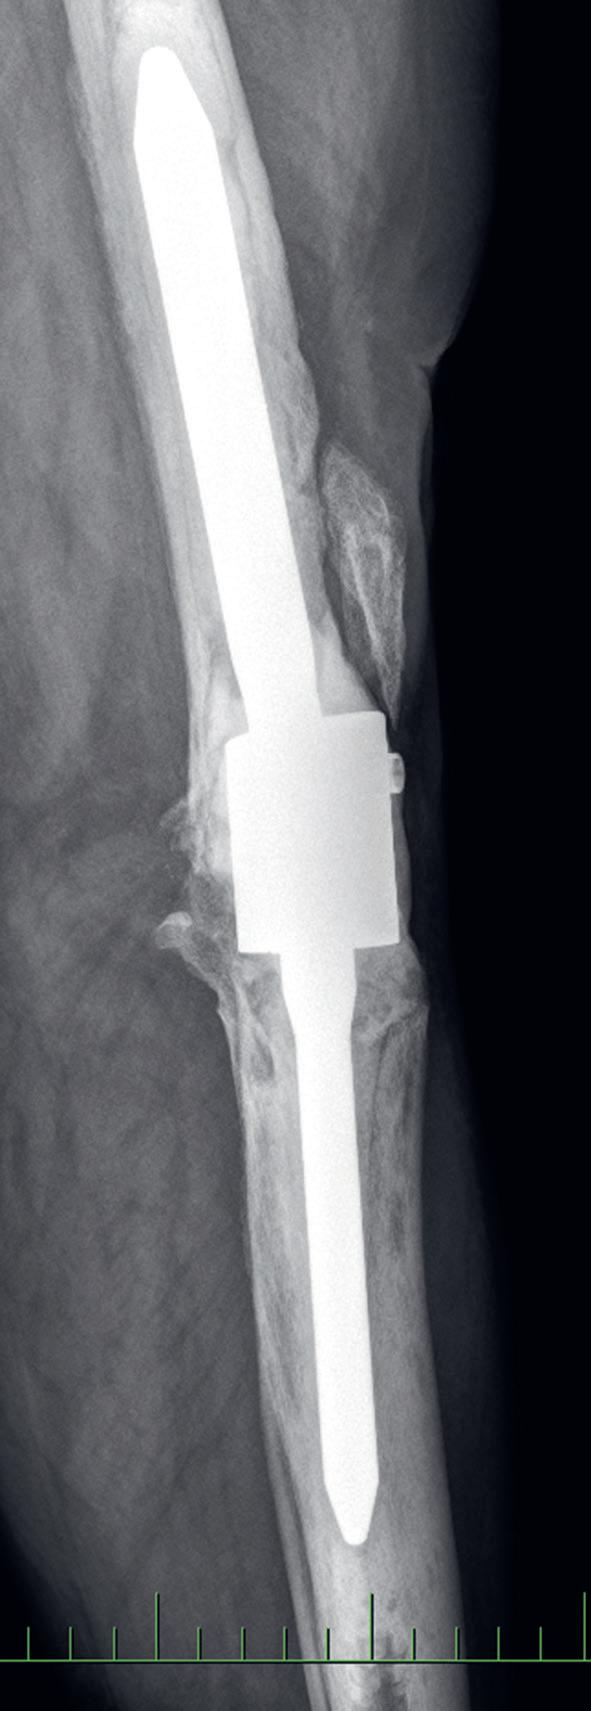

Osteotomie má za cíl korekci kloubní osy se změnou zátěžových oblastí kloubu. Operace obnoví osu končetiny a odlehčí tlak na poškozenou oblast kloubu a zmírní tak subjektivní obtíže nemocného. Příznivý výsledek obvykle přetrvává několik let. Dle poruchy osy rozlišujeme osteomie valgizační (korekce genu varum) a varizační (korekce genu valgum). V praxi se provádí klínovitá osteotomie s vytětím kostního klínu, sesazením obou fragmentů a fixací osteosyntézou (tzv. closed wedge osteotomie, obr. 19.5). Druhou možností je provedení jednoduché osteotomie s rozevřením obou fragmentů v klínovitém tvaru a fixace osteosyntézou (tzv. open wedge osteotomie, obr. 19.6). Dále podle anatomické lokality osteotomie rozlišujeme osteotomie distálního femuru (obr. 19.7) nebo proximální tibie. Artrodéza (ztužení kloubu) se primárně používá ve výjimečných případech (obr. 19.8). Je však možným řešením zejména po selhání aloplastiky, pokud není možná implantace nové náhrady. Vzhledem k faktu, že ztužení kloubu probíhá obvykle v terénu rozsáhlých kostních ztrát, používá se v poslední době ztužení kloubu pomocí implantátů – tzv. fúze kolenního kloubu (obr. 19.9). Nejde tedy v pravém slova smyslu o klasickou artrodézu – tedy kompletní primární kostní srůst femuru a tibie.

Obr. 19.9: Rentgenový snímek fúze kolenního kloubu pomocí implantátu v AP (a) a bočné (b) projekci